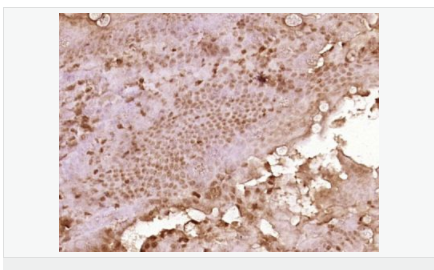

產品應用WB=1:500-2000 ELISA=1:5000-10000 IHC-P=1:100-500 IHC-F=1:100-500 ICC=1:100-500 IF=1:100-500 (石蠟切片需做抗原修復)

細胞定位細胞漿

產品介紹C3orf32 (chromosome 3 open reading frame 32), also known as fls485, is a 353 amino acid protein encoded by a gene that maps to human chromosome 3p26.1. Chromosome 3 is made up of approximately 214 million bases encoding over 1,100 genes. Notably, there is a chemokine receptor gene cluster and a variety of human cancer related loci on chromosome 3. Particular regions of the chromosome 3 short arm are deleted in many types of cancer cells. Key tumor suppressing genes on chromosome 3 encode apoptosis mediator RASSF1, cell migration regulator HYAL1 and angiogenesis suppressor SEMA3B. Marfan Syndrome, porphyria, von Hippel-Lindau syndrome, osteogenesis imperfecta and Charcot-Marie-Tooth disease are a few of the numerous genetic diseases associated with chromosome 3.

Tissue Specificity:

Expressed in enterocytes of small and large intestinal mucosa (at protein level). Expressed in enterocytes, chromaffine and interstitial cells.